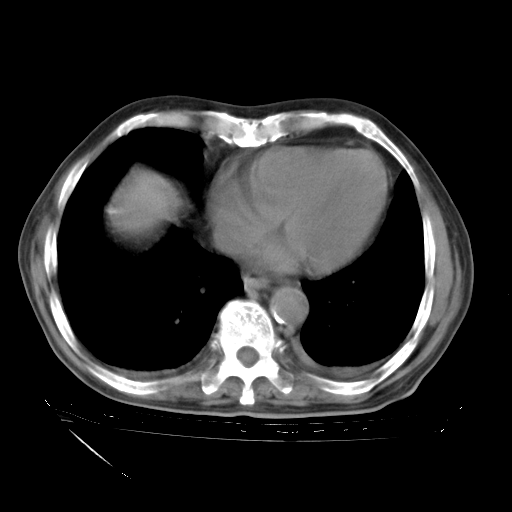

经过24天治疗,岳父的病情基本稳定。生活基本可以自理,可以下床活动。呼吸困难早已消失。体温基本正常。

只是甲强龙用80mg时血小板升到正常,改为60mg后又降到63×10*9/L。

主要治疗甲强龙80mg×14天,60mg×10天;同时抗结核(异烟肼+利福平+乙胺丁醇)。环磷酰胺0.1 tid 10天。

特别感谢胡教授、高管、桃子版主给出关键的治疗建议。桃版把所有肺部影像和全部临床资料请所在医院呼吸科、感染病科、结核科、临床免疫科专家会诊。临床免疫科专家制定了完整的治疗方案。